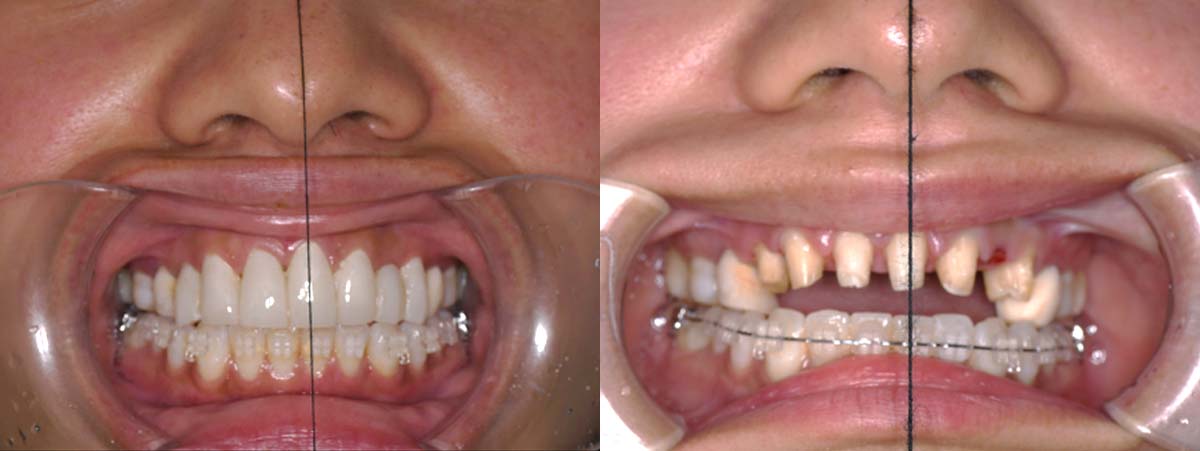

スプリント使用後、

補綴治療をした症例

副子なし 副子あり

バイトアップ後